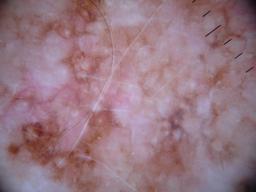

{

"age_approx": 55,

"anatom_site_general": "anterior torso",

"concomitant_biopsy": true,

"dermoscopic_type": "contact non-polarized",

"diagnosis_1": "Benign",

"diagnosis_2": "Benign melanocytic proliferations",

"diagnosis_3": "Nevus",

"diagnosis_4": "Nevus, Atypical, Dysplastic, or Clark",

"diagnosis_5": "Nevus, Clark",

"diagnosis_confirm_type": "histopathology",

"family_hx_mm": false,

"image_type": "dermoscopic",

"melanocytic": true,

"patient_id": "IP_5729601",

"personal_hx_mm": false,

"sex": "female"

}

"dermoscopic_type": "contact polarized",